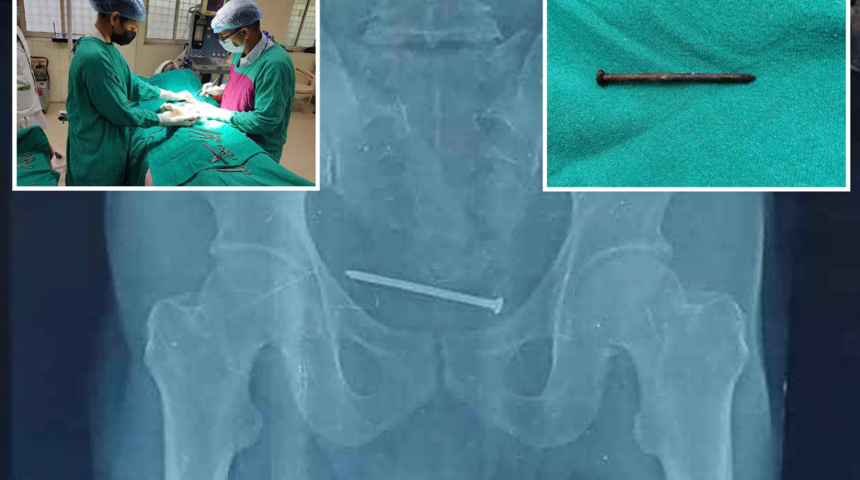

Hindistan’da mesane ağrısıyla doktora giden adamın mesanesinden 10 cm’lik bir çivi çıktı. 10 cm’lik çivinin bir yıldır adamın mesanesinde olduğu tahmin ediliyor.

Adı açıklanmayan hastanın mesanesinde yaşadığı dayanılmaz ağrı sonucu doktora başvurduğu öğrenildi. Hindistan Bölge Hastanesi’ne giden adamın röntgen sonucunu gören doktorlar, ağrının mesanedeki 10 cm’lik çividen kaynaklandığını fark edince afalladı.

Paslı çivinin adamın mesanesine nasıl girdiği bilinmiyor. Ameliyat olmaya bütçesi yetmeyen adamın ağrılarını dindirmek isteyen doktorlar, hastayı operasyona alarak çiviyi çıkardı.

Hastanenin “ilk” olarak tanımladığı operasyon yaklaşık bir saat sürdü. Operasyondan sonra iyileşen adamın hayatına normal bir şekilde devam ettiği belirtildi.